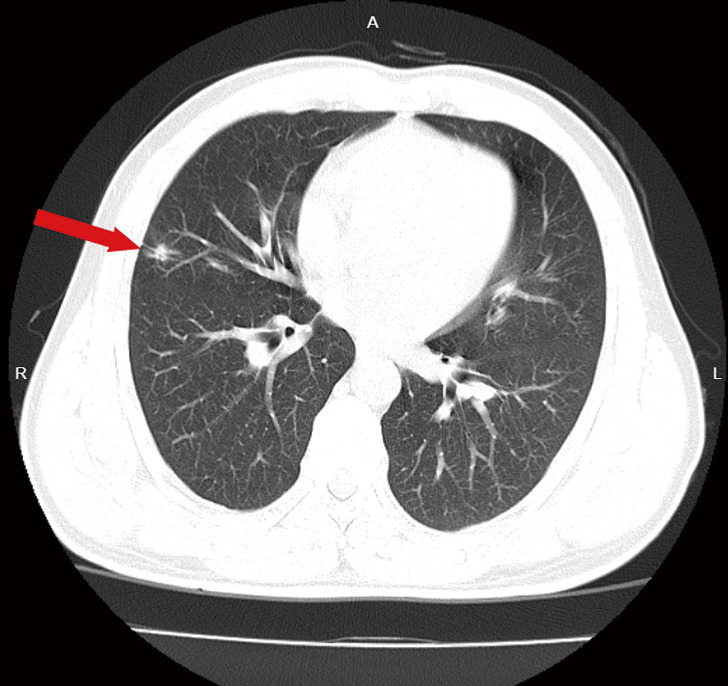

Case description: We report the case of a 49-year-old male who was diagnosed with stage IIIb (N2) lung adenocarcinoma. Next-generation sequencing revealed ROS1 fusions, and crizotinib was given simultaneously with targeted therapy during neoadjuvant chemotherapy. After 3 cycles of chemotherapy, surgery was performed, and the pathological results revealed major pathological response (MPR). Two years later, local and general examinations revealed no evidence of tumour recurrence.